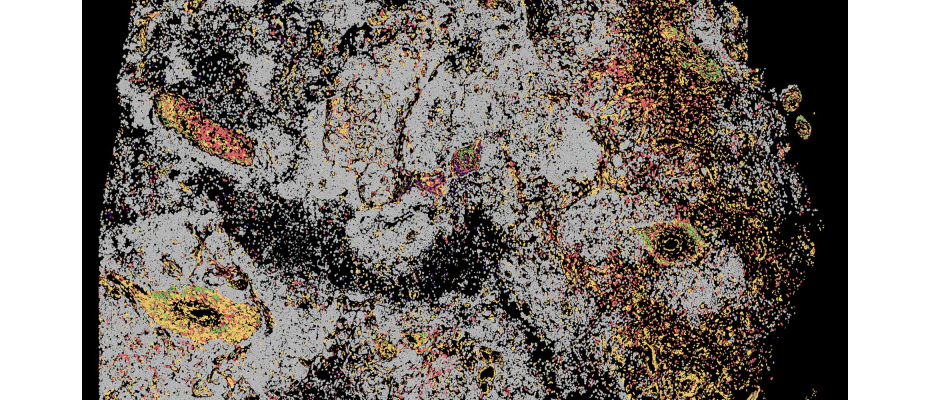

Los investigadores analizaron más de 70 000 células de pacientes con linfomas de líquido cefalorraquídeo, glioblastomas o metástasis cerebrales de melanoma, cáncer de mama y de pulmón, comparándolas con células de pacientes con trastornos neuroinflamatorios. El equipo de CNAG utilizó técnicas de secuenciación pioneras que permitieron estudiar individualmente el ARN de cada célula de líquido cefalorraquídeo, revelando cómo se activan los genes y cómo responden las células al tumor, incluidos los receptores de células T, que actúan como «sensores» para detectar y atacar el cáncer, y cuya expansión refleja la intensidad de la respuesta inmunitaria. El análisis se complementó con ADN tumoral para identificar posibles vulnerabilidades y transcriptómica espacial para generar un mapa detallado de las células en su entorno.

Imagen: crédito foto de portada: CNAG